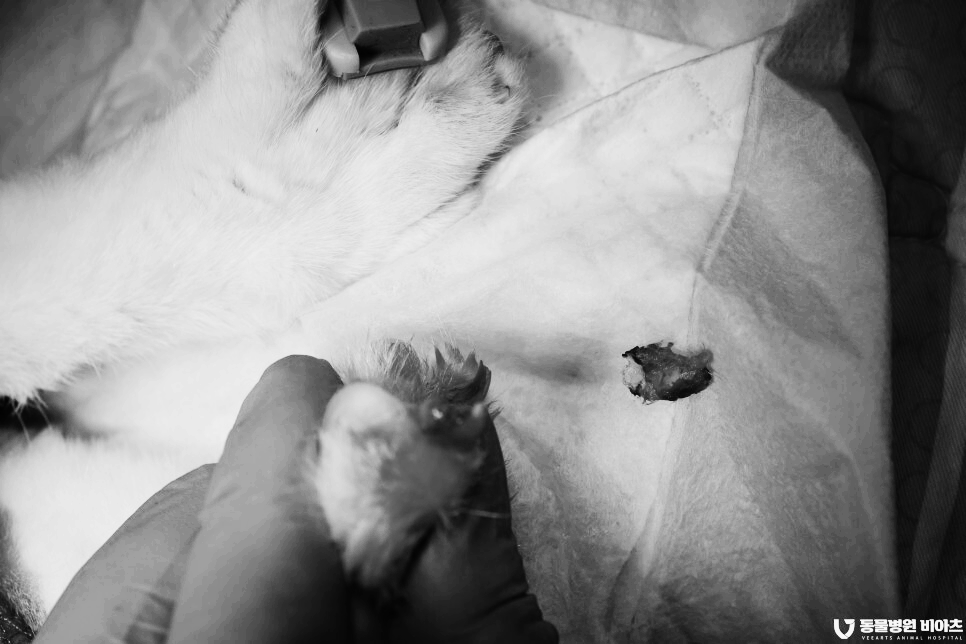

치료 (호흡 마취, 부분 골절된 발톱/ 육아종 제거)

골절된 발톱 부위에

염증이 많습니다.

염증이 생겨서 벌어진 틈으로 육아종이 증식하였습니다.

또한 출혈도 발생하고 있습니다.